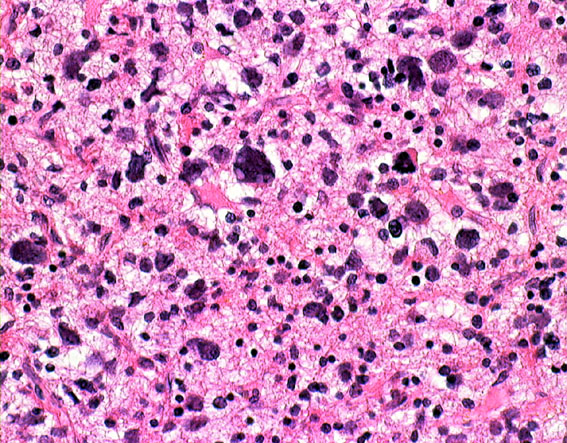

HE染色では細胞核の周りが抜けるような典型的なhalo(左側の写真)があります。1p/19q欠失があり,MIB染色率(右側)は4%でした。

同じ患者さんからの2カ所の病理標本です。左は乏突起膠腫グレード2と診断できますし,右は退形成性星細胞腫グレード3と診断できます。光顕診断では,両方合わせて,退形成性乏突起星細胞腫グレード3となります。ちなみに,olig2 強陽性,MIB-1 9%,1p/19q codeletionがありました。遺伝子診断を加えると退形成性乏突起膠腫となります。乏突起膠細胞系腫瘍では,術中迅速病理診断や定位脳生検術での診断は誤診を招くことが多くて危険です。

部分像だけでは星細胞系腫瘍と見分けはつかない

この部分のみを一見するとanaplastic astrocytomaです。しかし,他の大部分がoligoastrocytomaであり,かつての組織診断ではanaplastic oligoastrocytoma AOA WHO grade IIIです。

左側の病理像はanaplastic oligodendroglioma AO あるいはoligodendroglioma ODです。しかし,右の画像の様にpseudopallisading (necrosis)を示す部分があり,WHO grade 4と診断したくなるのですが,oligodendrglioma grade 3 ではnecrosisが混在してもgrade 3としてよいのです。